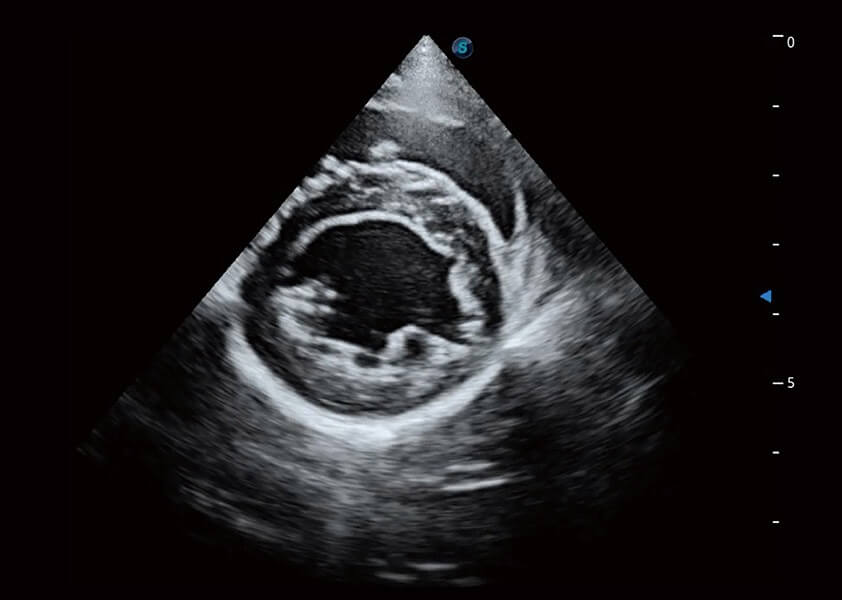

ProPet 60 作为一款高端台式动物超声设备,为动物医生的日常诊断提供了一系列贴合动物临床需求、解决临床实际问题的高级成像功能。凭借全系列高清探头,满足医生对腹部、心脏、生殖、浅表、肌骨等成像的所有需求,切实帮助您提升检查效率,提高诊断信心。

动物是人类最亲密的朋友和最值得信赖的伙伴。db真人体育官网也一直致力于探索动物专用的超声影像解决方案。 全新推出的ProPet系列,是db真人体育官网在动物超声影像智能化、专业化、精准化的一次跨越式革新。动物不能用言语来表述自己的不适,通过超声影像,ProPet系列搭建了动物医生与不同物种沟通的“桥梁”,为动物医生注入了“治愈之力”。